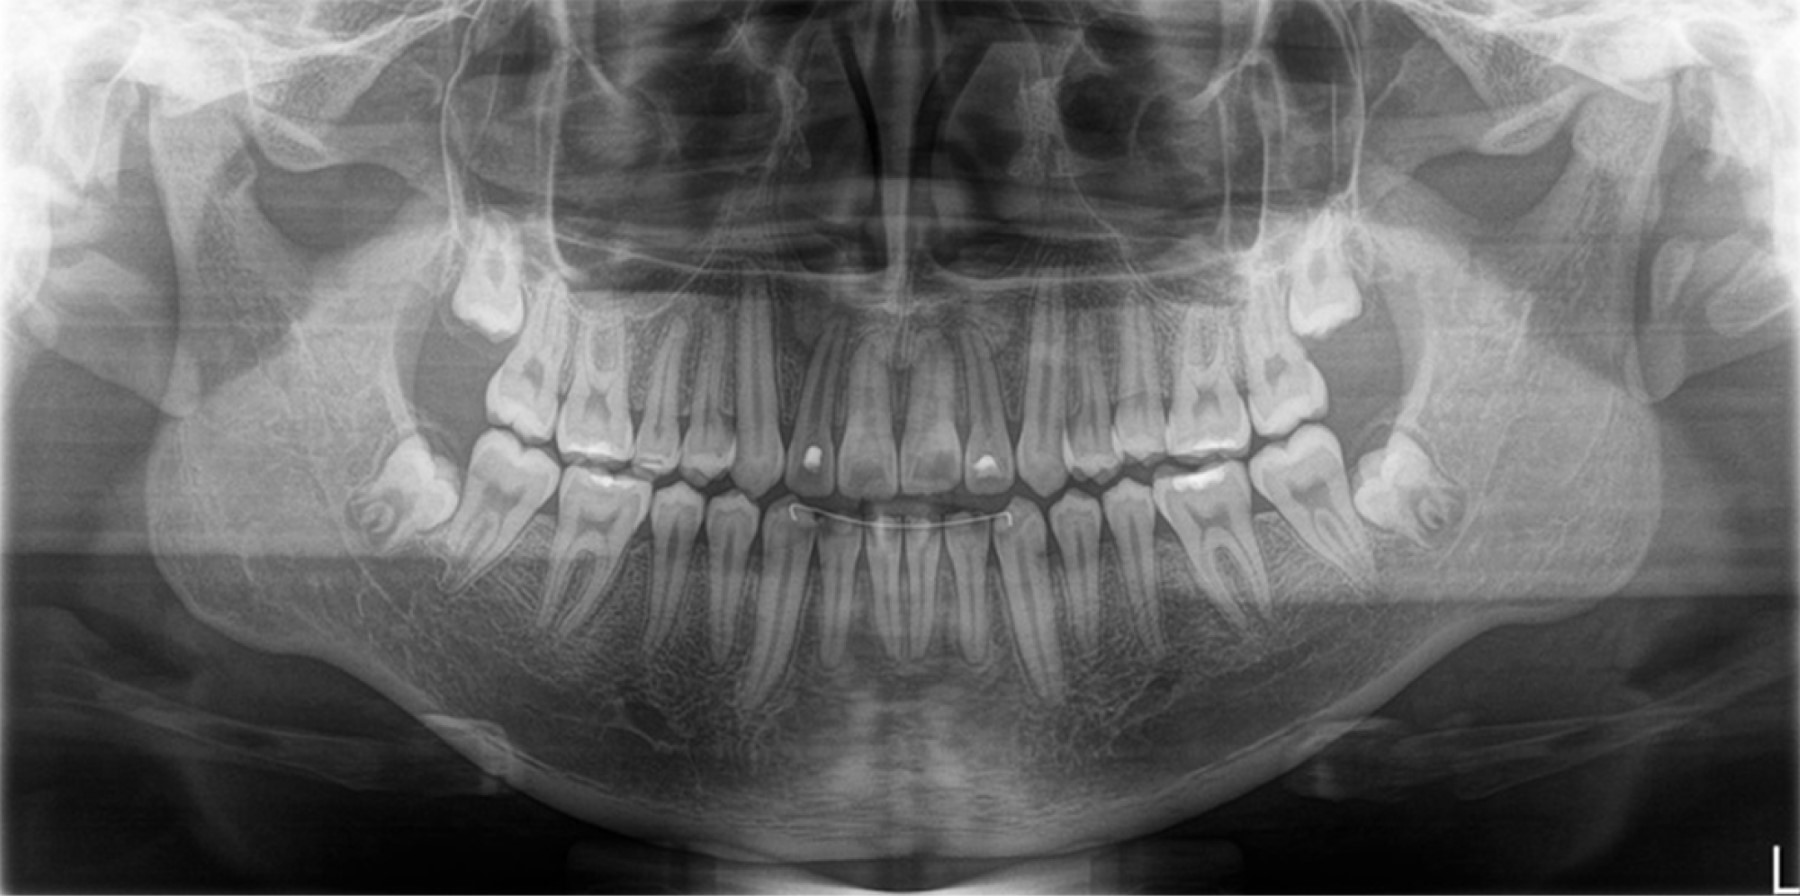

According to the extraoral and intraoral photographs (Figures 1 and 2), radiographic studies (Figures 3 and 4), and cephalometric data (Table 1), orthodontic treatment with traction of dental organs #11 and #21 was decided in order to fulfil the planned objectives. The treatment was carried out in three phases.

The duration of treatment was 48 months, the position of dental organs #11 and #21 was adequate, the overbite was corrected, bilateral class I canine and class I molar were achieved, a positive arch smile, correct anterior guidance (overjet and overbite), coincidence of midlines, elimination of open bite in the anterior sector (Figures 5 and 6); the correct position of the dental organs #11 and #21 was observed in the radiographic examination, with no root resorption and, bone neoformation adjacent to the traction site (Figure 7).

Figure 3

Figure 4